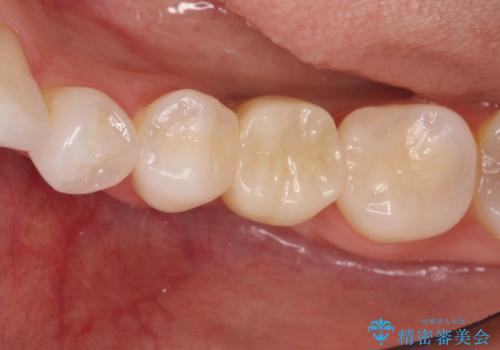

深い虫歯により抜歯となった奥歯 インプラント治療でかみ合わせを回復する

かぶせ物の種類:Bellezza screw retain